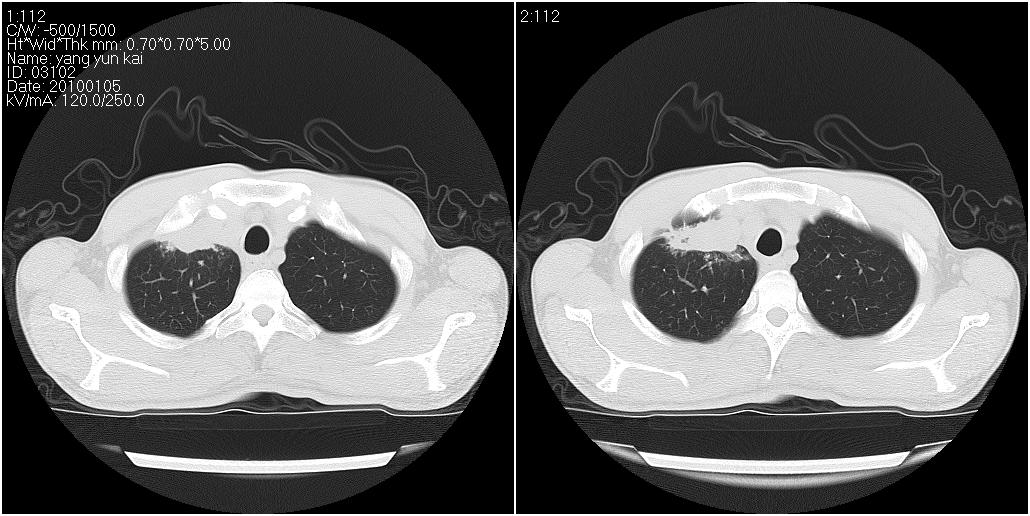

标题: CT23980:男性,47岁。近来咳痰、咳血,血沉增快(40左右),

男性,47岁。近来咳痰、咳血,血沉增快(40左右),痰中未检出结核杆菌。

两肺继发性肺结核并多发性结核球形成,部分病灶内空洞形成。

符合继发性结核表现部分空洞形成并播散